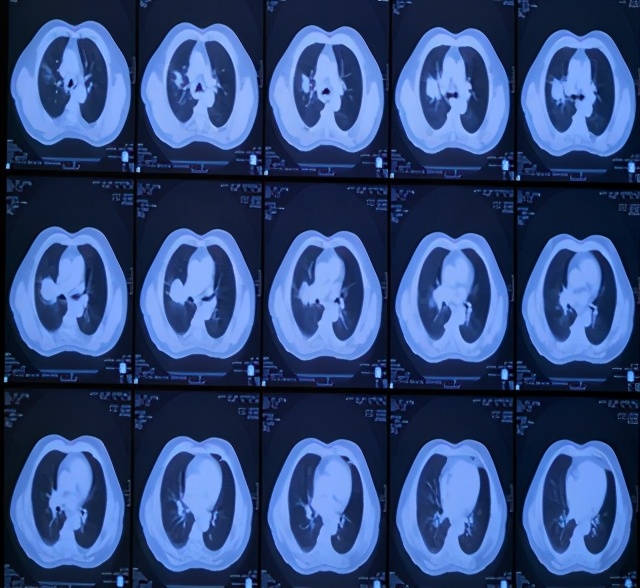

患者刘某某,男,65岁, 13年前因咳嗽、咳痰带血半年就诊,胸部CT示右上肺占位,支气管镜示右上叶前段支气管远端狭窄,活检病理:中低分化鳞癌。诊断:右上肺中低分化鳞癌,T4N1M0,IIIB期。

因二次全麻下气管插管出现哮喘无法手术,于2007年5月30至2007年6月28日进行局部放射治疗,同时给予对症支持治疗。照射剂量PTV(肿瘤外5mm)66GY/22f/30d;GTV(肿瘤边缘)70GY/22f/30d;GTV1(肿瘤内部)77GY/22f/30d;治疗期间,咳嗽缓解、无咯血,血常规 基本正常 范围,按计划完成治疗。

治疗后5年复查,患者偶有咳血,局部病灶纤维化改变

治疗后11年复查,无明显活动后 气喘 。